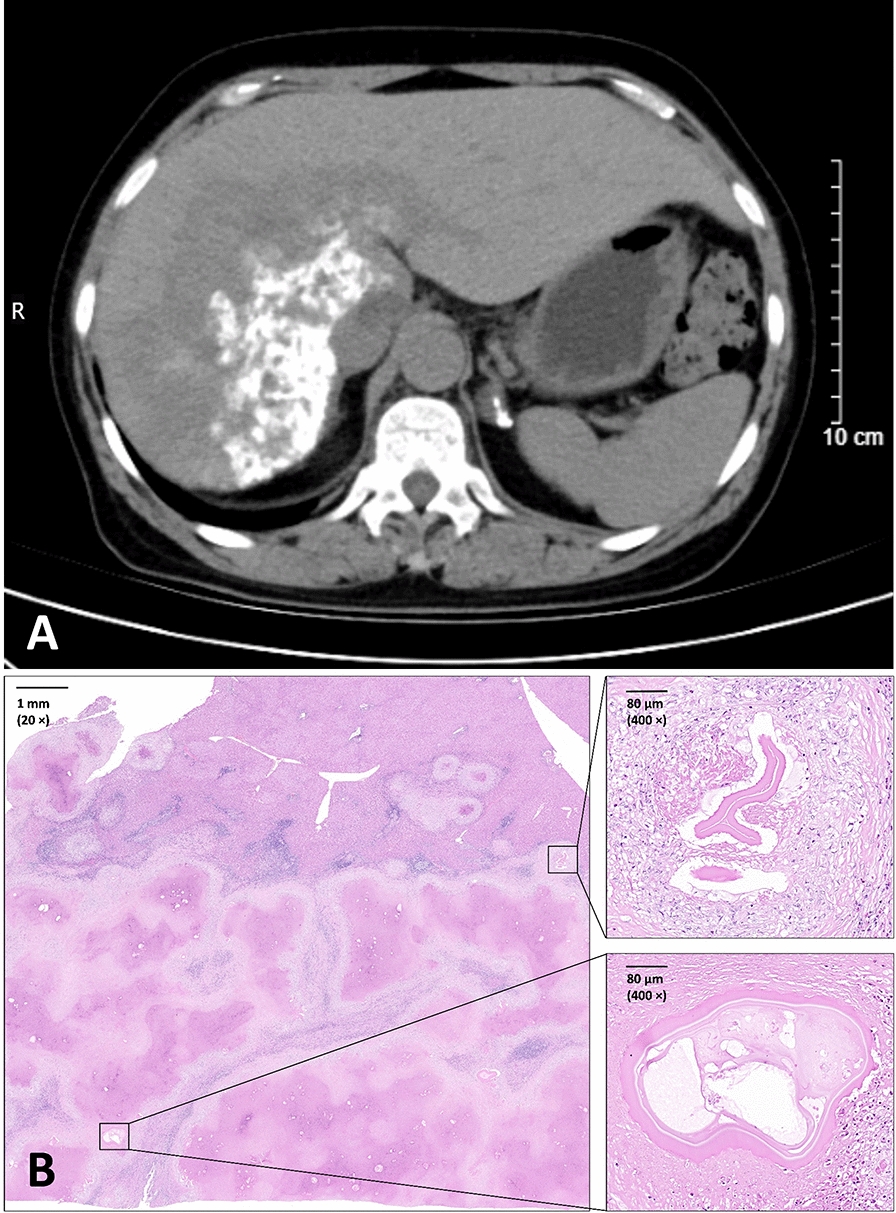

Case presentation: A 58-year-old female pastoralist from Inner Mongolia, who had no endemic region exposure history but prolonged occupational contact with dogs, presented with severe AE. Clinical examinations revealed a massive hepatic lesion exceeding 10 cm in diameter, accompanied by elevated eosinophils (0.90 × 109/L) and basophils (0.08 × 109/L). Despite undergoing liver transplantation, the patient succumbed postoperatively. Histopathological confirmation and molecular phylogenetics identified the Mongolian genotype of E. multilocularis infection, distinct from the predominant Asian genotype in China. Potential evidence of zoonotic transmission was discovered through genotype-matched E. multilocularis detection in corsac fox (Vulpes corsac) feces from the grasslands along the shores of Hulun Lake (Hulun Buir City, northeastern Inner Mongolia, China).